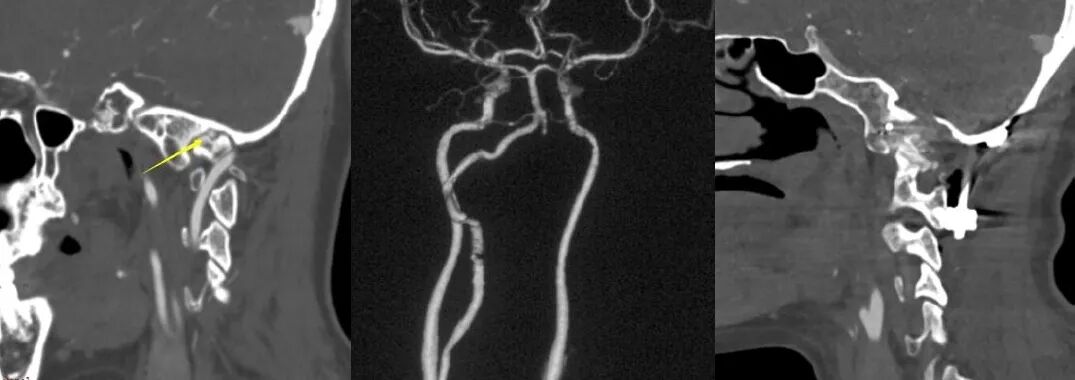

颅颈交界区骨性结构畸形常常伴有椎动脉走行异常,特别是寰枕融合畸形。当寰枕融合畸形发生时,寰椎后弓、两侧侧块、横突与枕骨融合消失,导致椎动脉V3段穿过枢椎横突孔后便失去了寰椎横突孔和寰椎后弓等骨性结构的引导,进而出现走行异常,椎动脉直接向内侧跨过枢椎椎弓峡部进入椎管。椎动脉V3段走行异常会遮挡寰枢椎关节面的后方(图8),增加了从后路在进行寰枢椎关节间操作和寰枢椎椎弓根置钉过程中损伤椎动脉的风险。

术前常规进行头颈部CTA扫描,应用计算机软件(推荐应用RadiAnt DICOM Viewer, Medixant Co.)对CTA Dicom数据进行三维重建详细观察颅颈交界区骨性结构畸形和椎动脉走行,制定手术方案,评估椎动脉损伤的风险。

根据进行关节间操作时损伤椎动脉的危险程度,将椎动脉走行分为3种类型:低风险型,高风险型,禁忌型低风险型椎动脉:椎动脉走行不遮挡寰枢椎关节面,进行关节间操作损伤椎动脉的风险较低,此类患者通常没有寰枕融合,或寰枕融合不完全,寰椎保留横突孔结构,椎动脉受到寰椎横突孔的引导,走行路径正常,没有遮挡寰枢椎关节面(图9)。

Ⅰ型高风险型椎动脉指患者一侧椎动脉走行异常,手术中损伤几率较高,但对侧椎动脉走行、管径正常,手术中损伤几率较低。手术中高风险椎动脉发生损伤,对侧低风险椎动脉可以代偿基底动脉血运,患者发生后循环缺血的风险较低(图10)。

Ⅱ型高风险型椎动脉,指两侧椎动脉皆为高风险型椎动脉,由于两侧椎动脉均走行异常,因此术中均存在较高损伤风险,如两侧椎动脉同时被损伤,患者可能发生后循环缺血(图11)。

Ⅲ型高风险型椎动脉,指患者一侧椎动脉为高风险性椎动脉,而对侧椎动脉退化或缺如,一旦高风险型椎动脉损伤,对侧椎动脉无法代偿基底动脉血供,可引发致命性基底动脉缺血(图12)

对于高风险型椎动脉,我们采用的治疗策略是将椎动脉向头侧抬起。显露寰枢椎关节后缘后,将关节间撑开器完全插入关节,如此,在旋转撑开器对关节间隙进行撑开的过程中,与椎动脉接触的是撑开器柱状的连接杆,避免对椎动脉造成卡压和切割,降低椎动脉损伤的风险(图13)。

禁忌型椎动脉:椎动脉穿行于寰枢椎关节面,进行寰枢椎关节间操作必然损伤椎动脉(图14)。这种椎动脉走行方式在关节间操作过程中尚无有效办法避开,因此是关节间撑开操作的禁忌证。